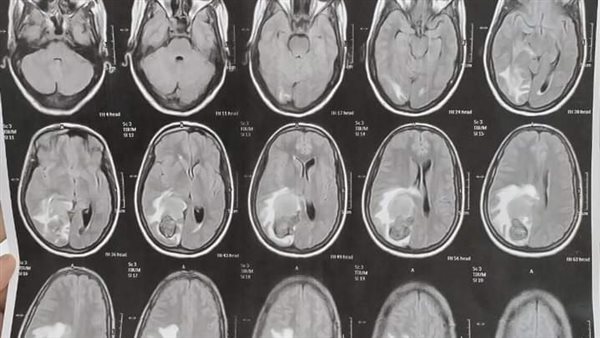

أجرى الفريق الطبي بنجاح جراحة لمريضة عمرها 28 عاما تعاني من صداع مستمر، وبمناظرة الأشعات تبين وجود وحمة دموية كبيرة نافذة ضاغطة على مركز الحركة، وعلى الفور تشكل قام الفريق الطبي بقيادة الدكتور محمد عبد الباسط خلاف رئيس قسم جراحة المخ والأعصاب ومدير المستشفى، يعاونه الدكتور محمد سيد عبد العال مدرس التخدير والعناية المركزة، والطبيب مصطفى كاشف مدرس مساعد جراحة المخ والأعصاب، وتم إجراء الجراحة و استئصال كامل للوحمة الدموية، بواسطة الميكروسكوب الجراحي وجهاز الأشعة التليفزيونية على المخ مع الحفاظ على جميع المراكز الحساسة بالمخ.